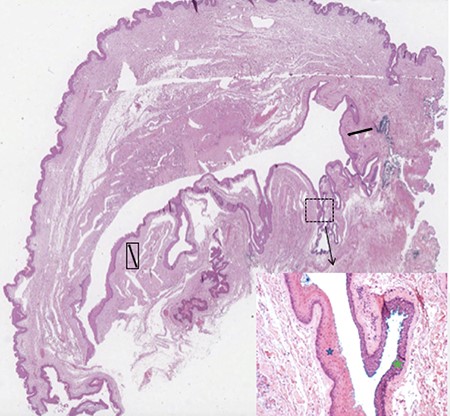

The cyst was examined under anaesthesia in the lithotomy position and was mobilized into the intersphincteric space and excised preserving the perianal skin (Fig. 2). The cyst was excised entirely and macroscopically appeared to be a thin-walled 8-cm long sac containing a yellow fluid. The resulting skin defect was closed with interrupted 2-0 vicryl dissolvable suture material. Histological analysis of the mass confirmed a large hybrid epidermal inclusion cyst (Fig. 3).

Microscopic overview of the surgical specimen showing a large hybrid epidermal inclusion cyst (black arrows) lined by squamous epithelium (blue star) with areas of transitional epithelium (green star; haematoxylin and eosin stains).